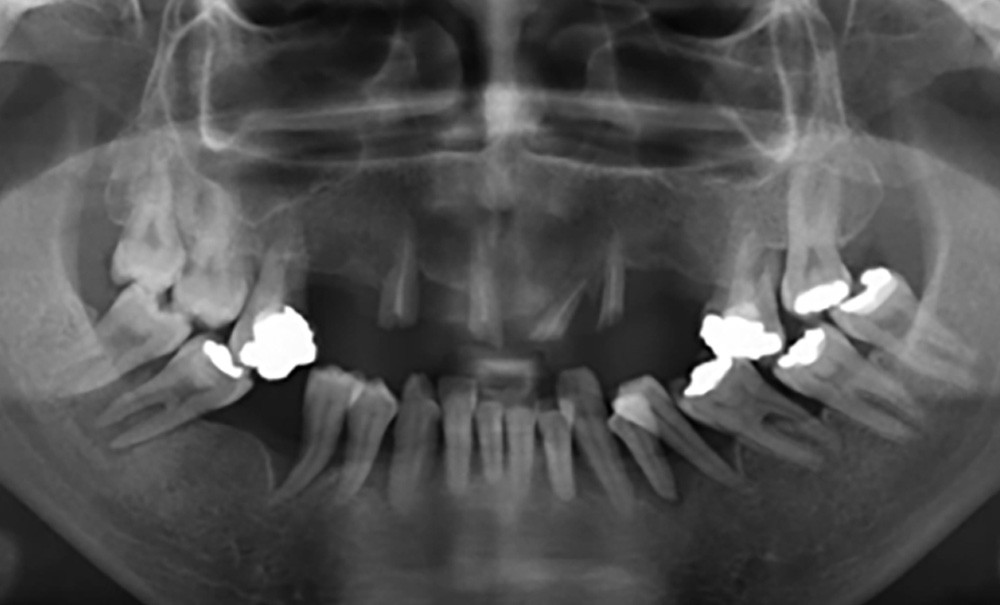

L’objectif de ce travail est de souligner, à travers des cliniques, les intérêts multiples qu’offre la prothèse supra-radiculaire dans la gestion des édentements de classes II et IV (Kennedy-Applegate) de grande étendue.

Édentement antérieur de grande étendue : classe IV de Kennedy-Applegate

La problématique biomécanique des édentements antérieurs de grande étendue est essentiellement liée à un porte à faux important des dents prothétiques en dehors du polygone de sustentation. En effet, l’aire de sustentation (AS) est…